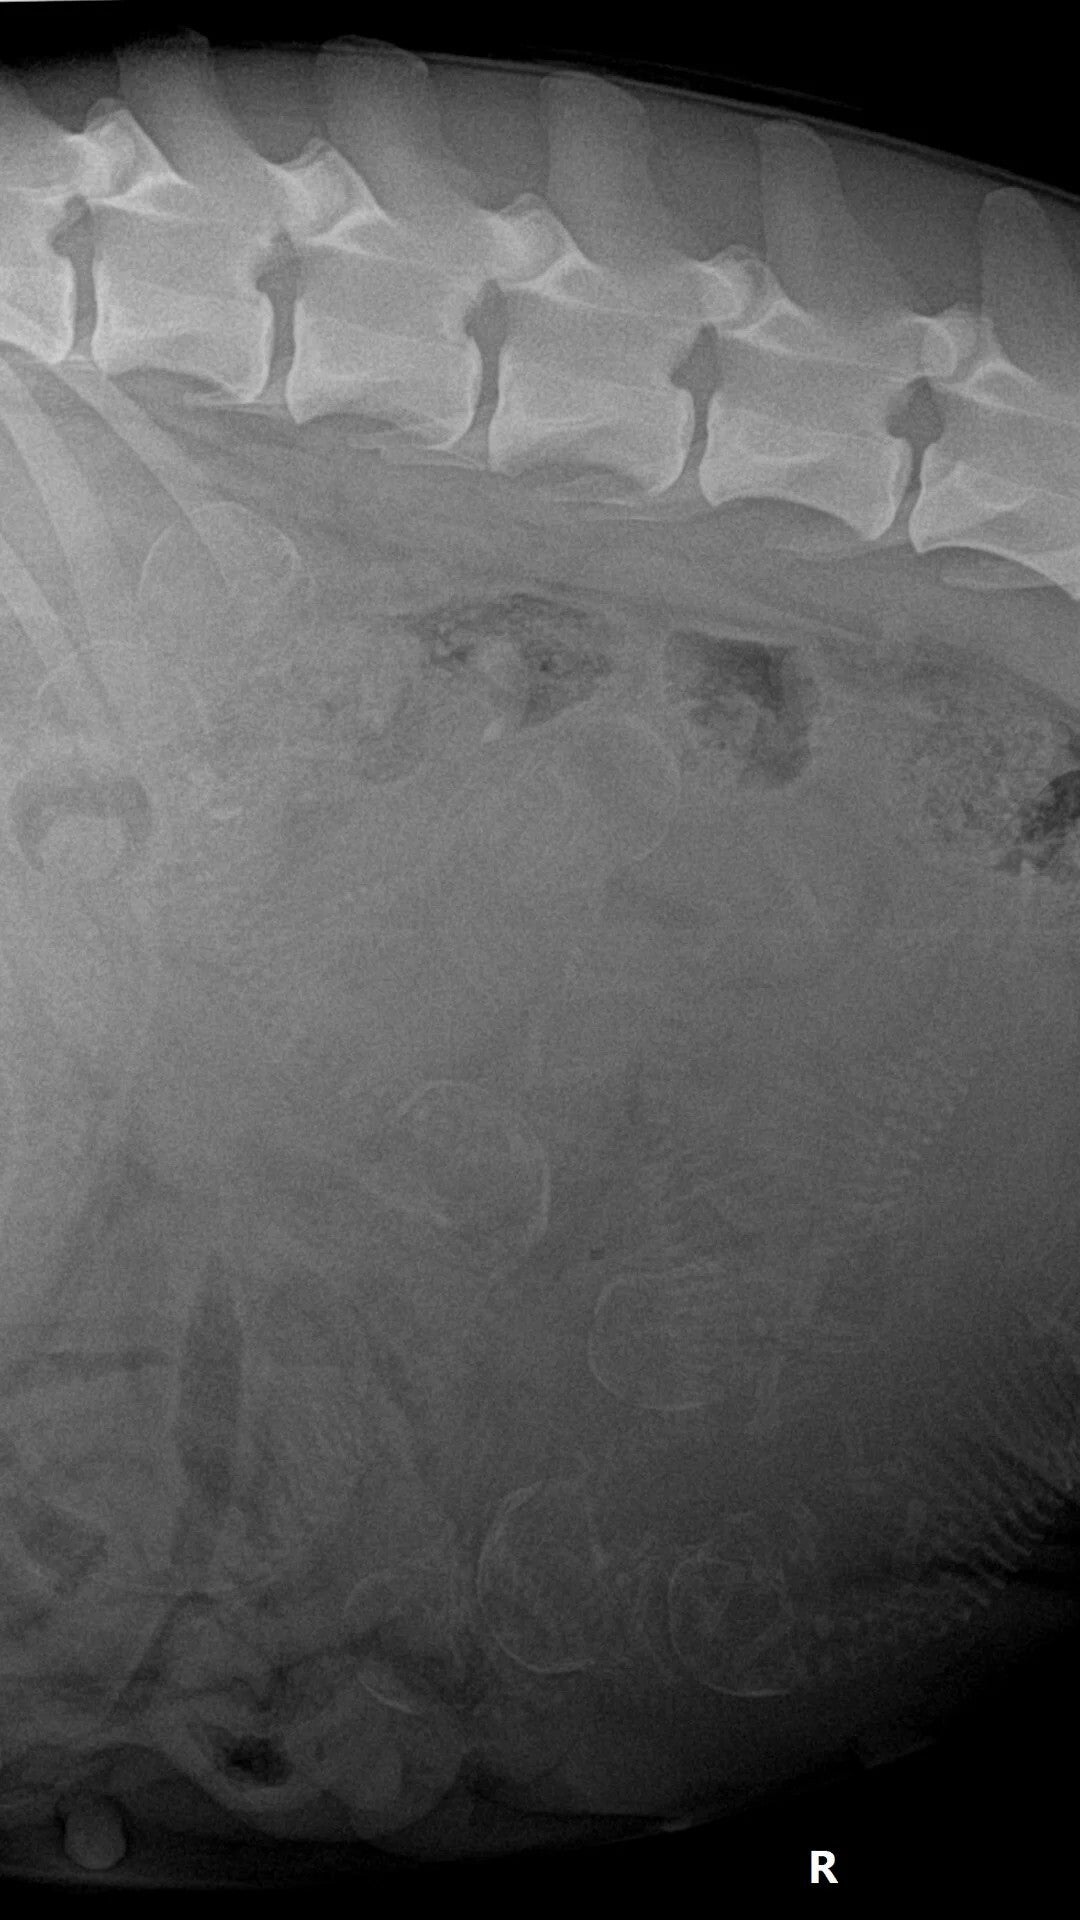

2 april zijn we weer bij de dierenarts geweest om een rontgen foto te maken.

Zodat we een beetje een idee hebben hoeveel pups we kunnen verwachten.

We hebben er 8 geteld. Beetje druk in de buik van Jiulia.

Het blijft spannend.........